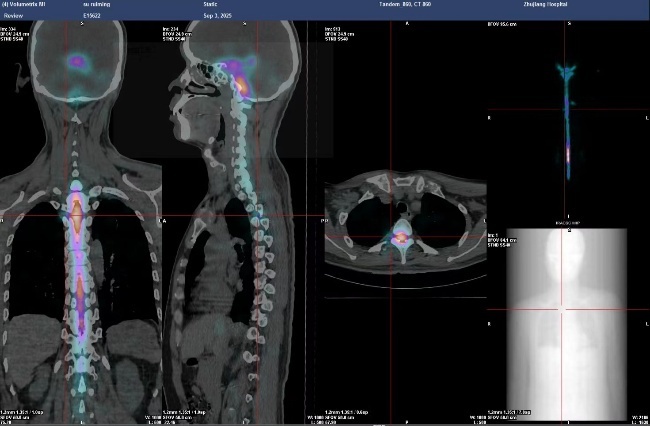

入院后,陈镇洲讲授团队速即为苏先生张开病因探查。胸椎磁共振成像(MRI)查验露出“椎管后缘静脉丛膨胀”,脑脊液漏导致静脉代偿性膨胀。脑脊液漏口常荫藏在脊柱椎管内,定位难度不小。通过精确的核素脑脊液扫描获胜定位了“罪魁首恶”——位于胸椎段的两个明确的脑脊液漏口。